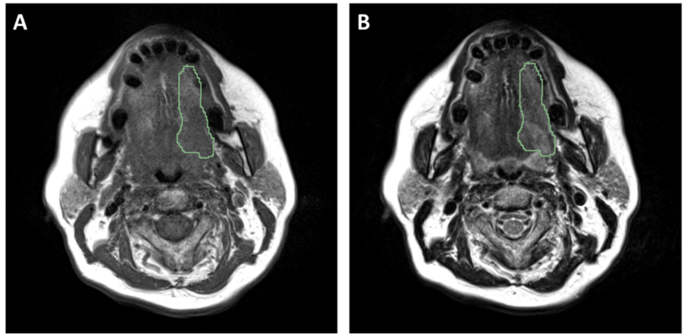

3.2 MRI图像预处理与放射组学特征提取

实验目的是标准化MRI图像,减少成像异质性,提取可重复的放射组学特征。研究对T1/T2加权MRI图像进行多步骤预处理:采用3D高斯滤波去噪,N4ITK算法校正磁场不均匀性,Z-score法进行强度标准化,最后将体素重采样至2mm各向同性分辨率;使用Pyradiomics工具从预处理后的图像中提取1072项放射组学特征(T1、T2加权各536项),涵盖形状大小、一阶统计、纹理、小波变换等多个类别。预处理步骤有效降低了不同中心、不同扫描参数导致的图像异质性,提取的特征覆盖了肿瘤的形态、纹理等多维度信息,为后续特征筛选提供了丰富的数据基础。